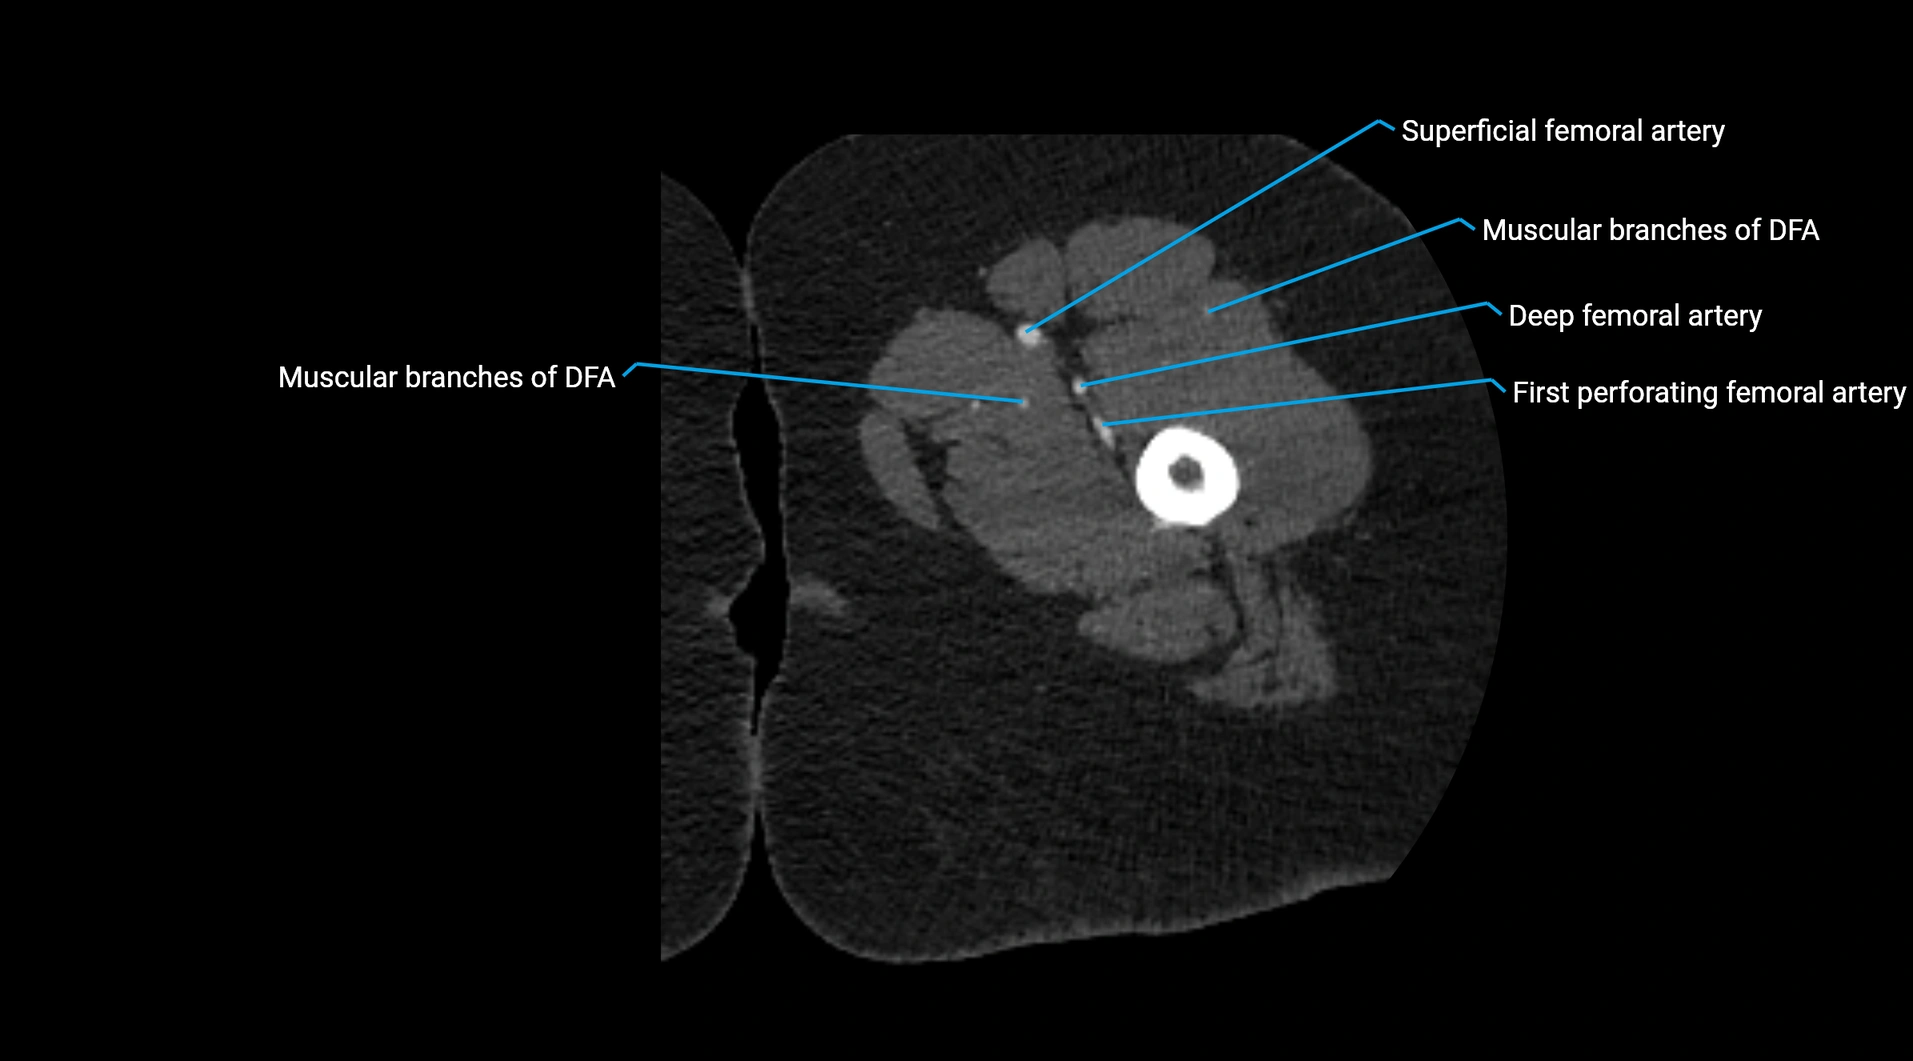

CT images

image

Contrast-enhanced CT (CTA):

• Gold standard for abdominal aortic imaging

• Provides excellent detail of lumen, wall, aneurysm, thrombus, and branch vessels

• Multiplanar and 3D reconstructions help in aneurysm measurement, stent graft planning, and dissection evaluation